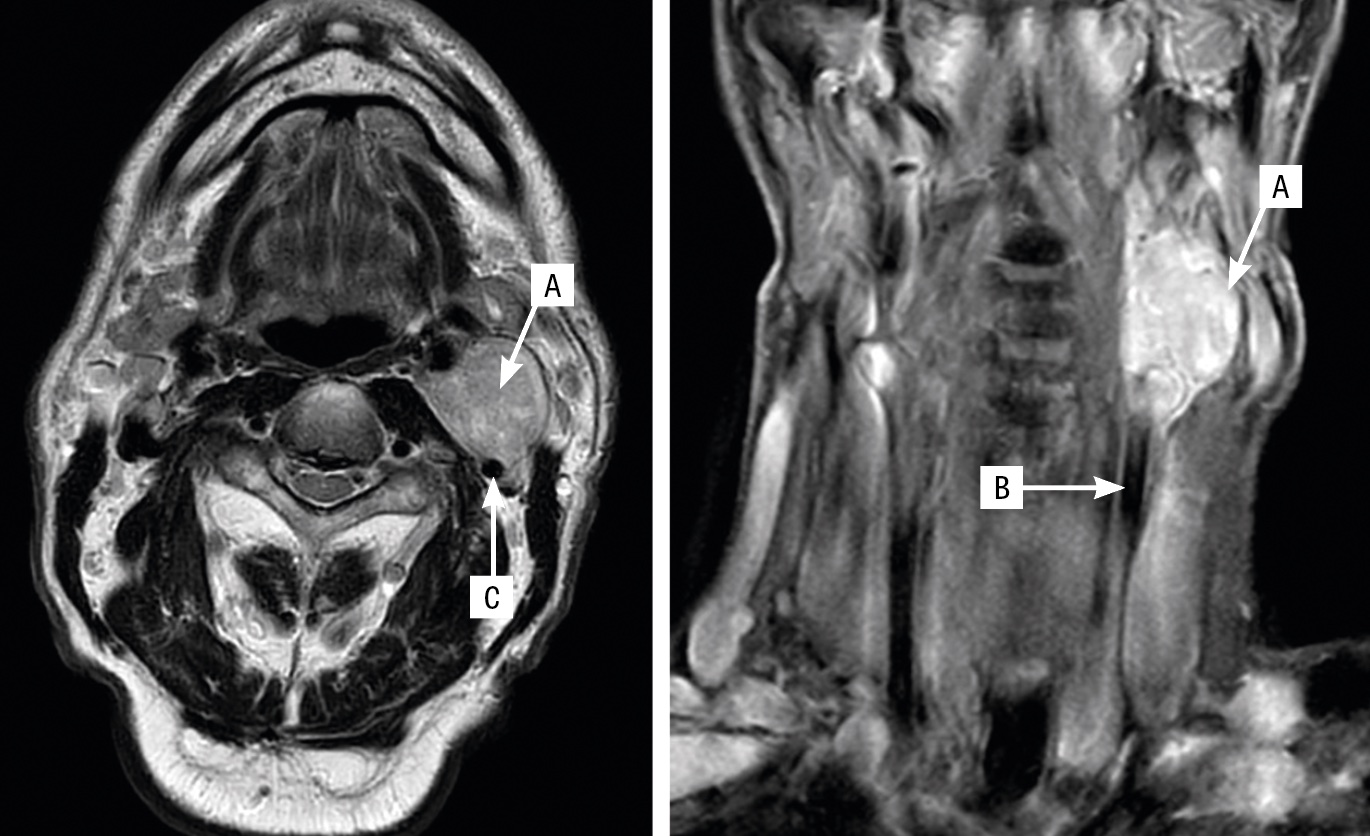

Översikt Vid stark misstanke om glomustumör ska patienten remitteras till en av Sveriges två nationella högspecialiserade enheter